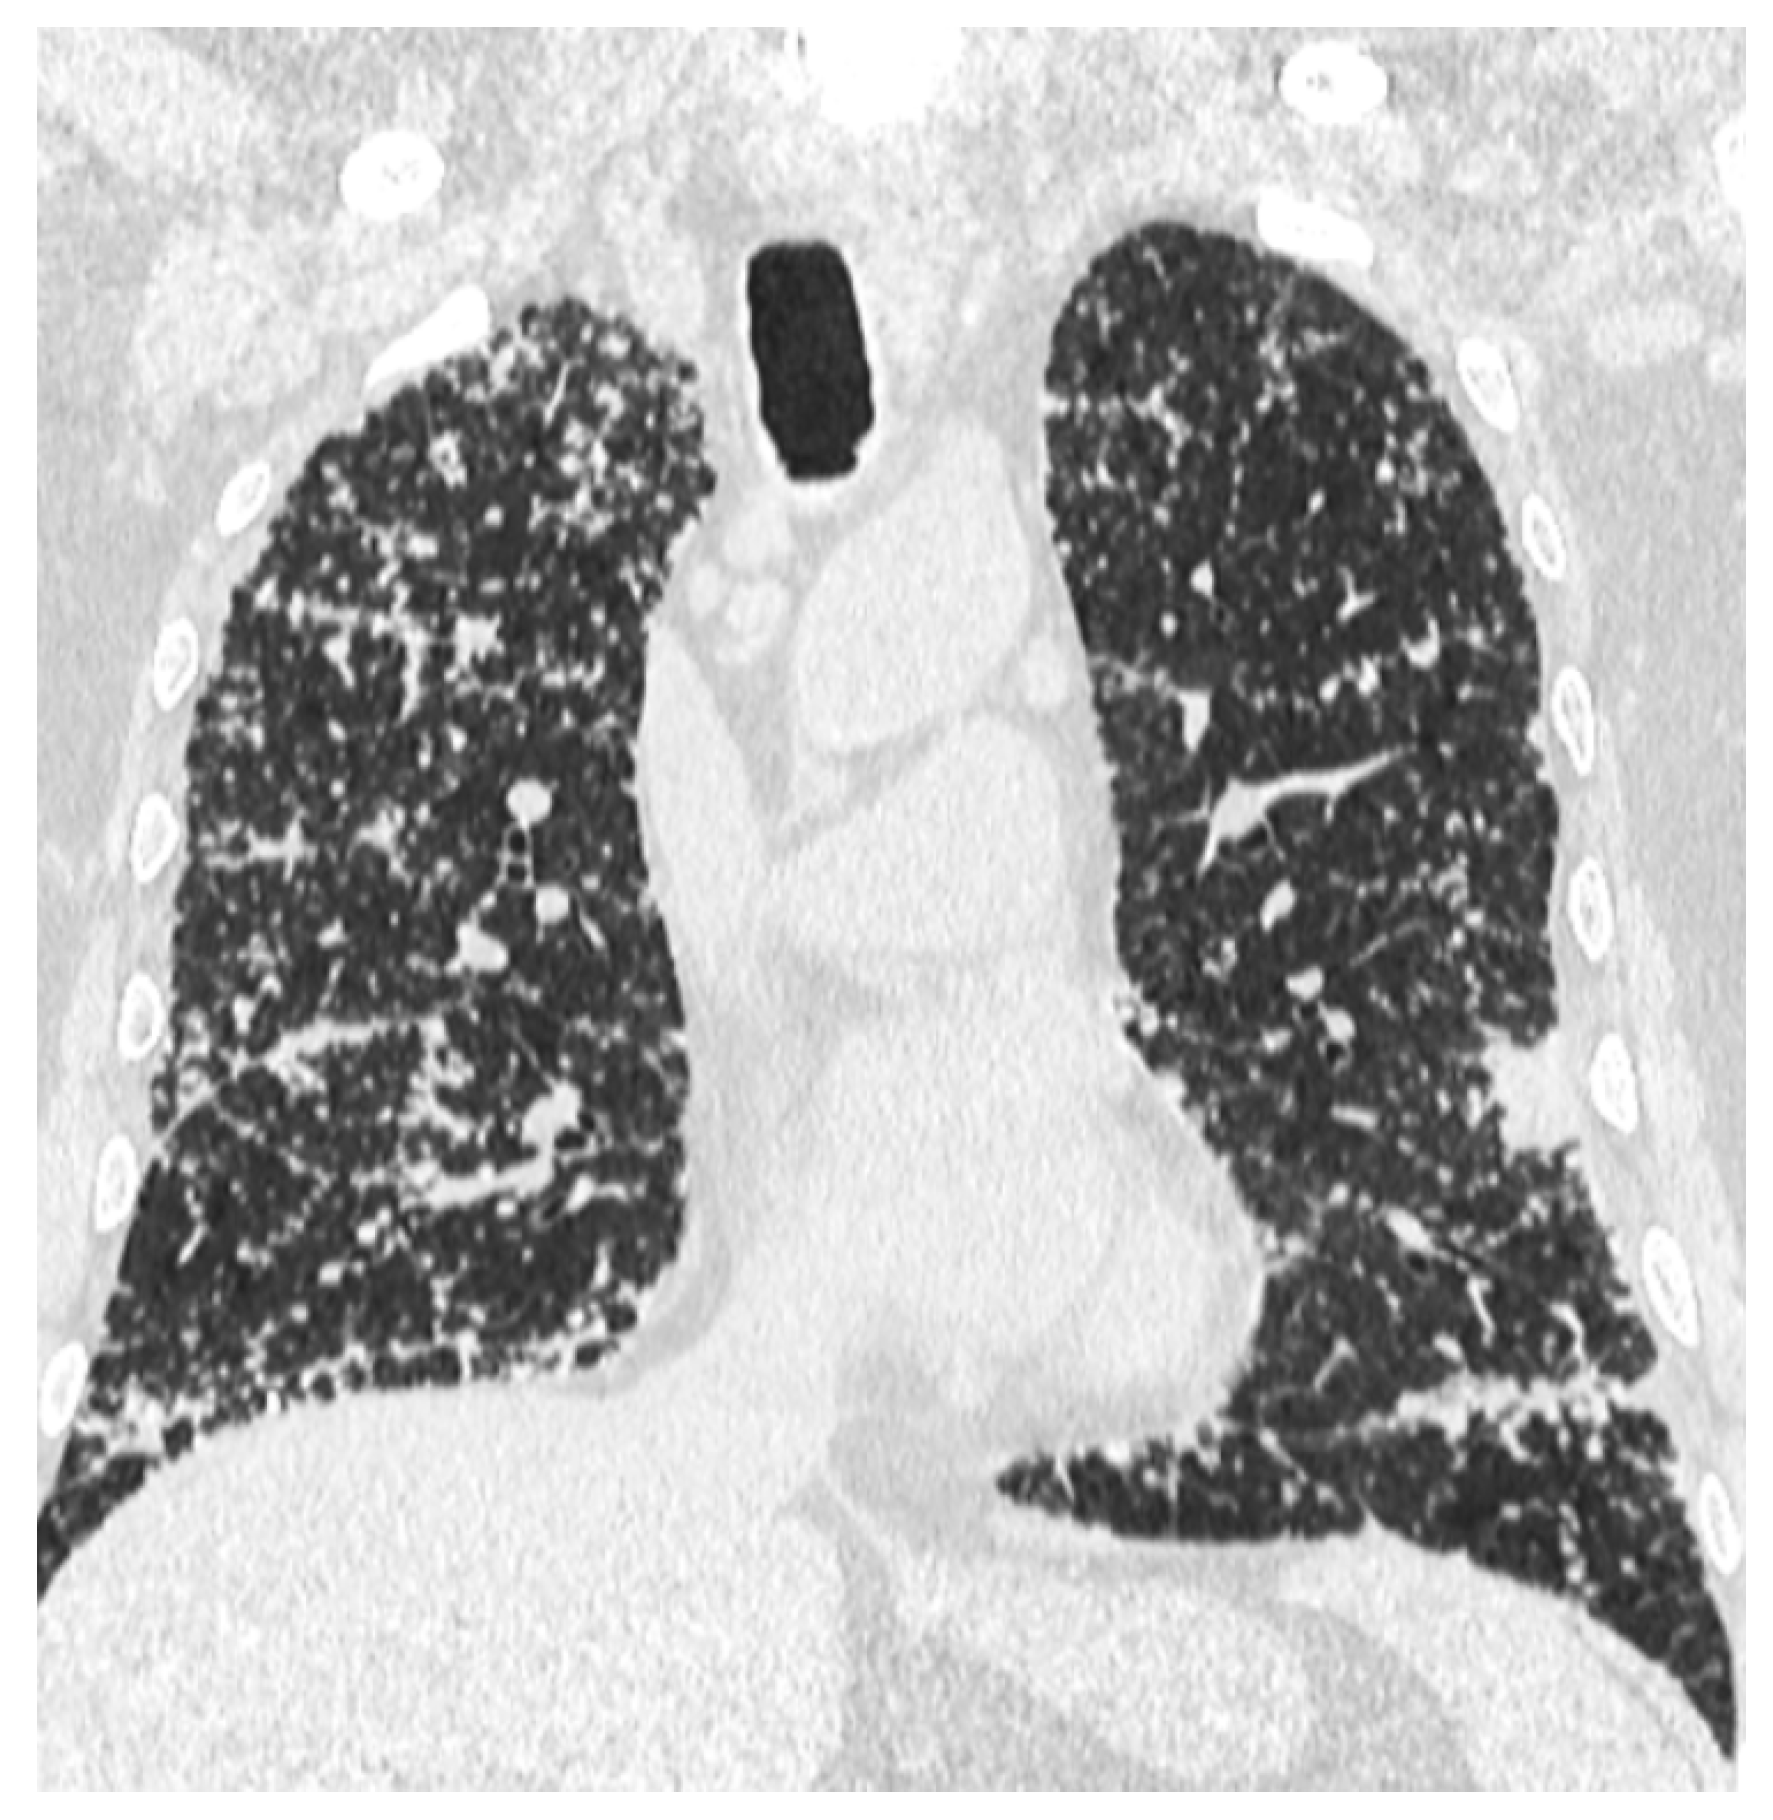

A whole-body contrast enhanced CT scan was subsequently performed, which demonstrated a 6/2.8 cm heterogeneous cervical mass that enclosed the left thyroid lobe and isthmus, as well as the posterior side of the sternocleidomastoid muscle (with no clear demarcation line), and superior extension to the larynx and to the thyroid cartilage. Inferiorly, invasion to the superior mediastinum structures was noted. Chest CT revealed multiple bilateral pulmonary nodules, suggestive of metastasis, and lymphangitic carcinomatosis. Several cervical and mediastinal lymph nodes with a tendency to confluate were also involved (Figure 1, Figure 2, Figure 3 and Figure 4).

Figure 3.

Lymphangitis carcinomatosis of the lungs.